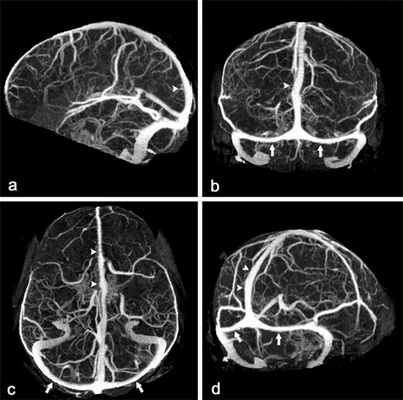

2. Флебография головного мозга

Проводится без применения контрастного вещества, поэтому побочных явлений, как правило, после исследования не возникает. Манипуляция длится около 20 минут и проходит, как при стандартном МРТ.

МР-флебография сосудов головного мозга

Пациента укладывают на подвижную кушетку, которая постепенно движется в центр магнитного кольца.

Томограф фиксирует сигналы, исходящие от анатомических структур головного мозга, и создает определенное изображение, на основании которого доктор может подтвердить — либо опровергнуть — предварительный диагноз.